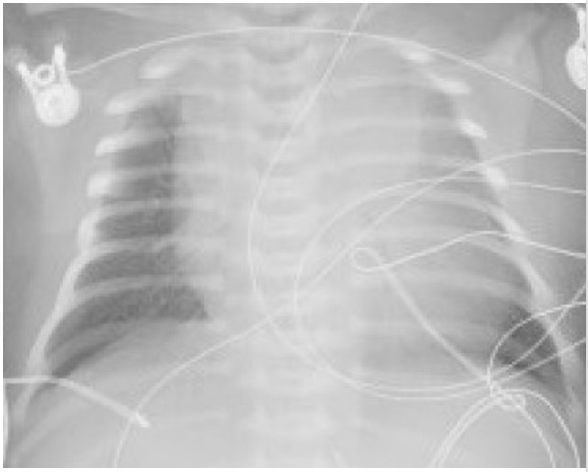

You order a blood gas test and a chest x-ray. The neonate’s x-ray is shown here. What is the pathophysiology of the most likely diagnosis?

Reading x-rays is difficult, but it looks like possible diffuse congestion on the left side? Which would line up with D, but I'm not sure

Could the left lung maybe have alveolar collapse because it's mainly just gray and not a lot of air seems to be getting in?

I am lacking in the ability to read x-rays, but it appears to me that the right lung is not filling the chest cavity. I chose C because it is the only one that truly indicates this x-ray findings. It does not appear that there is any edema because there would be more white due to fluid. It looks like the main problem is in one lung, so it probably would not be a problem with the epiglottis. I do not believe it would be related to A or E either

Is that an abnormally large cardiac silhouette or is that more like pulmonary congestion in the left lung?

I don't know how to read X-rays very well, but it does seem the right side of the heart seems larger than normal, which makes me think of some sort of fluid overload, whether it being pulmonary edema or interstitial edema (D or C).

I don't think that is the heart as it appears too large in comparison to the chest cavity. I think it is the lung?